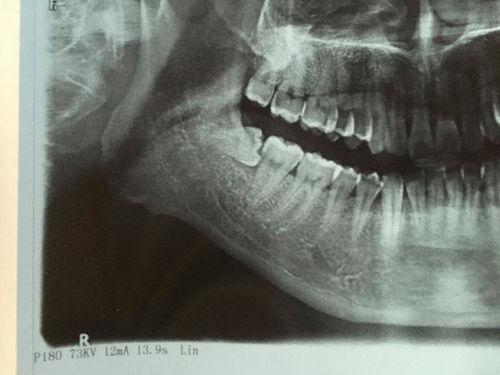

四、牙医的“魔法”:精准定位与巧妙操作

在拔阻生智齿的视频中,你会发现牙医们有着超凡的技艺。他们能够精准地定位智齿的位置,然后运用各种工具进行巧妙操作。有时候,他们会用牙挺将智齿撬出来;有时候,他们会用牙钳将智齿夹住,然后用力拔出。这个过程虽然痛苦,但却是必要的。